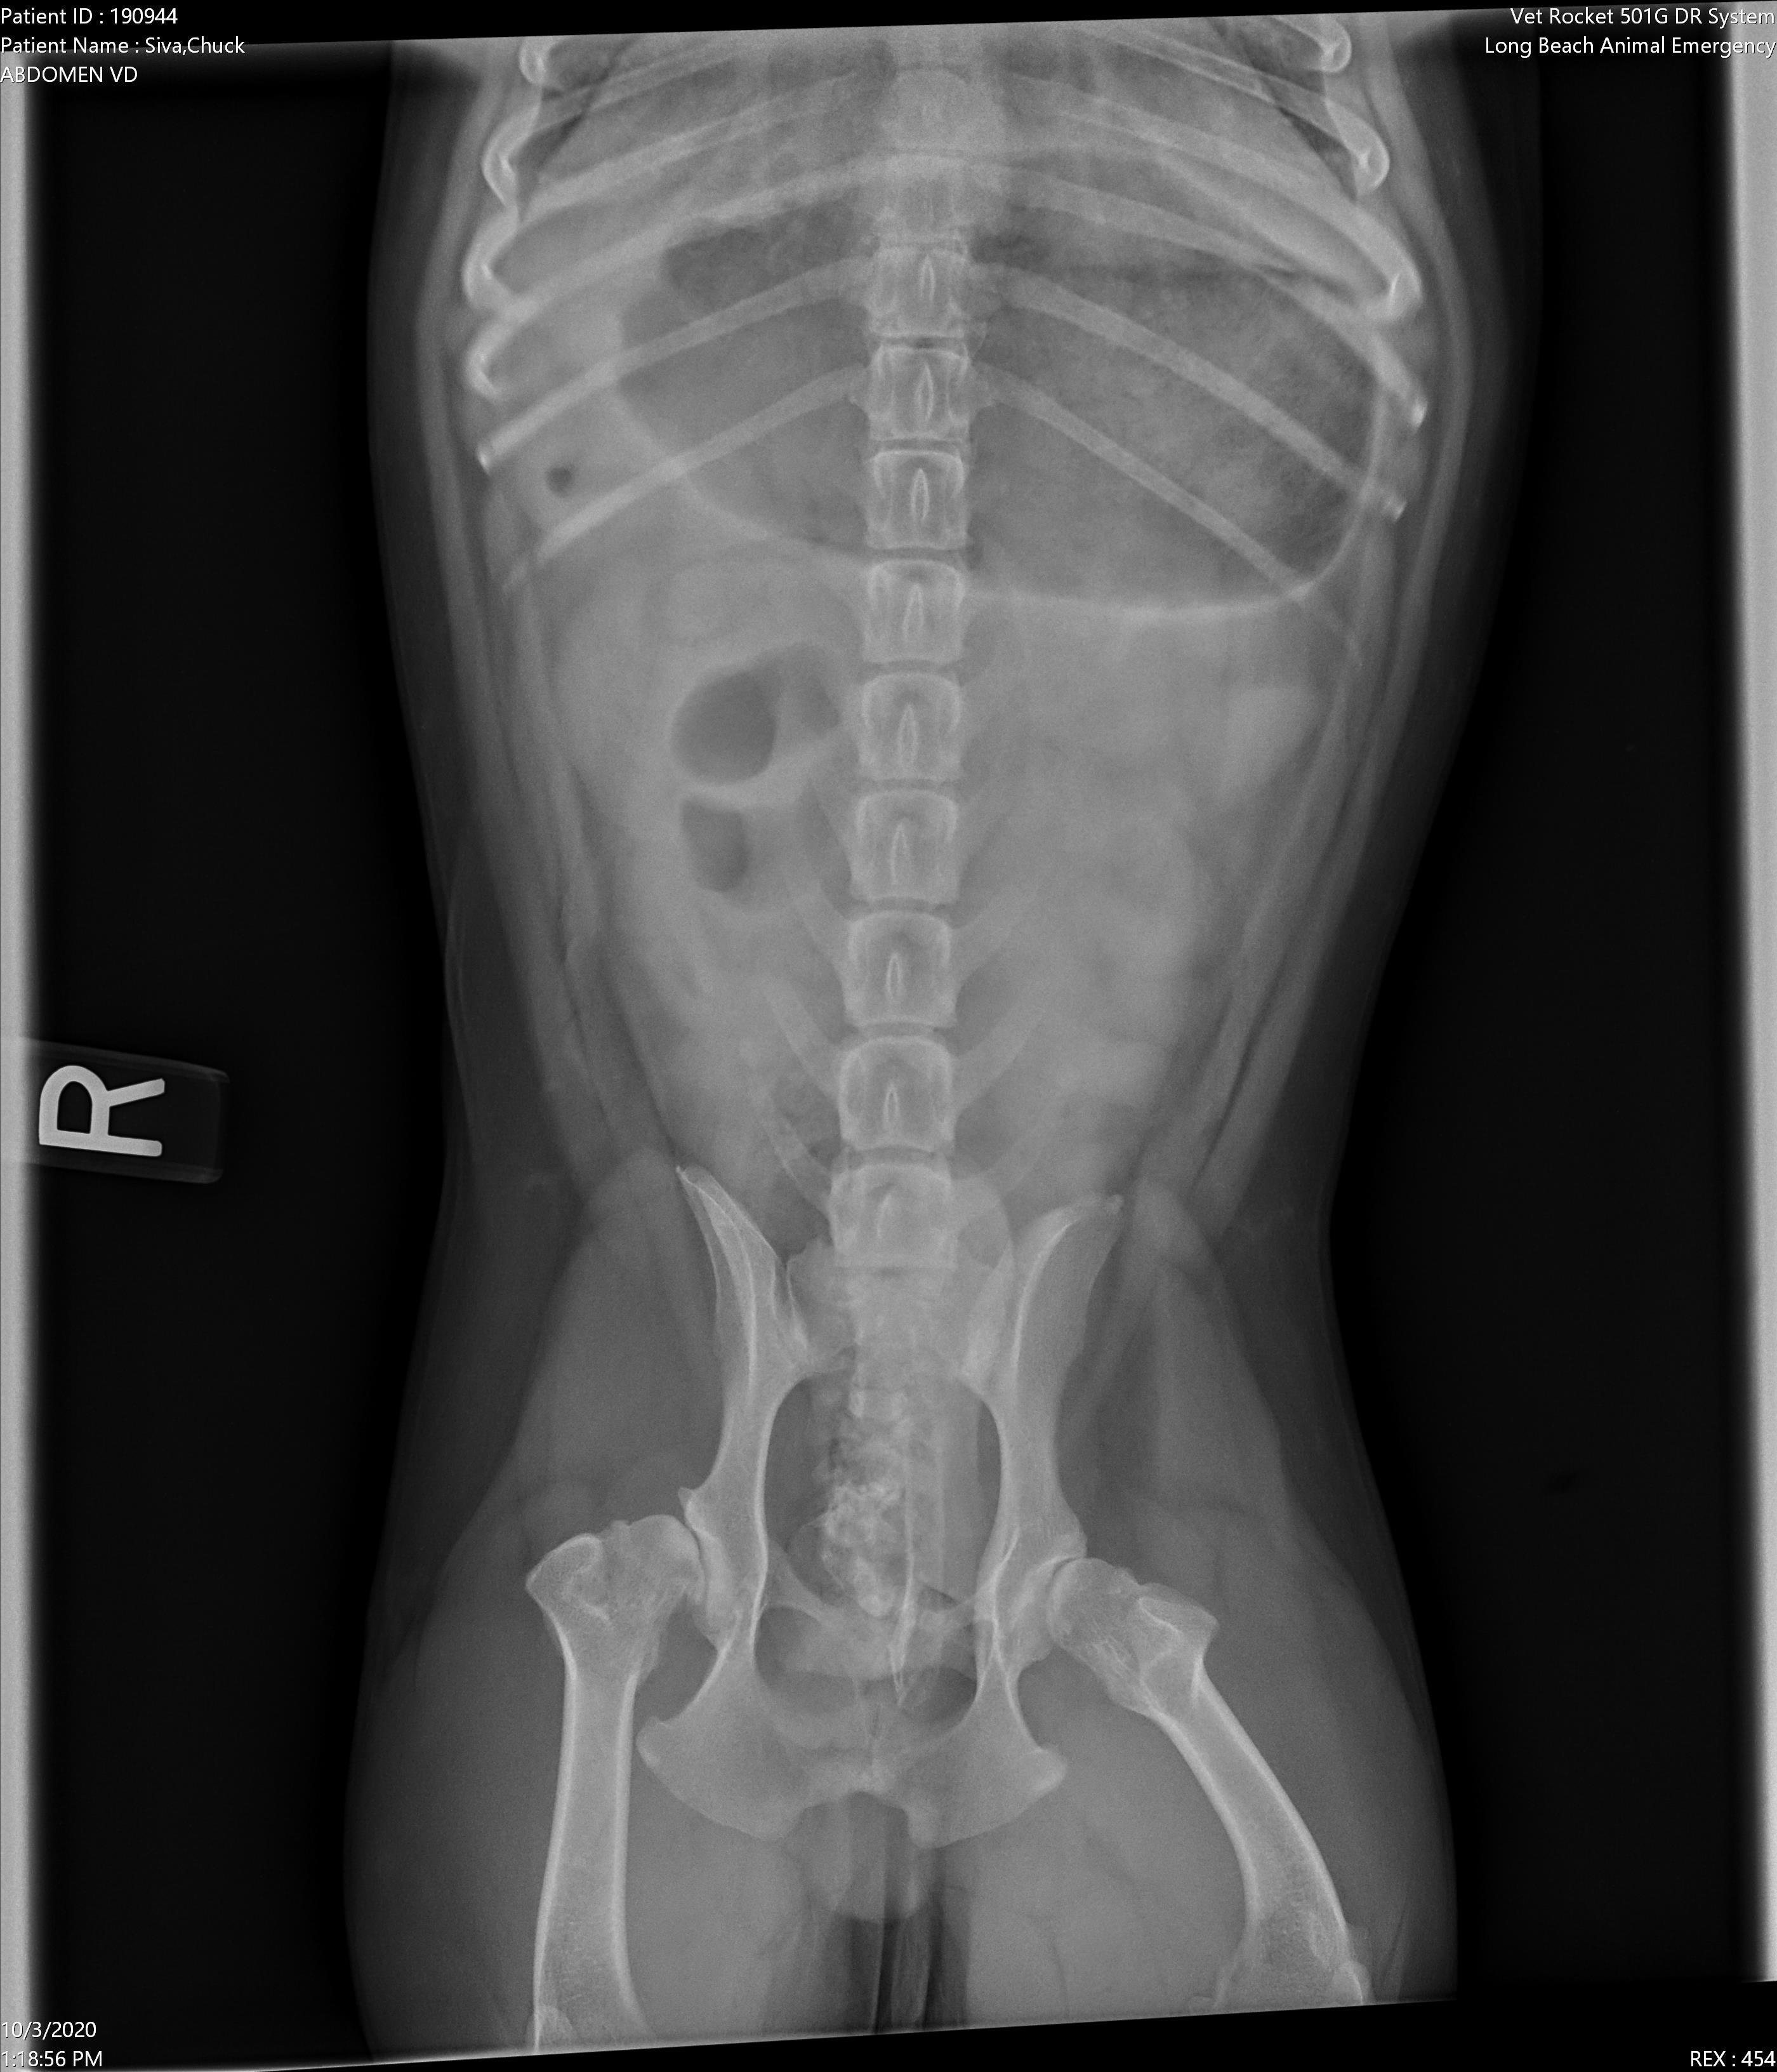

Pet's info: Dog | French Bulldog | Male | neutered | 5 years and 9 months old | 29 lbs

Hi! My 5 1/2 year old French Bulldog was taken to the emergency bc we noticed his leg was hurting him and started to pant and panic. The emergency vet told us that was the least of our worries and proceeded to tell us he had a brain injury even though it was all assumption and wanted us to put him down! This place is a scam! I demanded an X-ray and he is better now back at home but still need to treat his leg. Can you tell me if this hip displaisia, dislocation, arthritis or a fracture?

Poor guy. Your pet Chuck has severe hip dysplasia and possibly even early signs of arthritis. It is so severe that the femoral head doesn't even appear to be in the socket, creating a subluxation appearance as well. I would highly recommend having your vet send Chuck to an orthopedic specialist to get a treatment plan to help stabilize these joints for Chuck so that he does not succumb to a permanent debilitated state due to this defect. I am so sorry that you had to go through so much with your pet and I am glad that his condition is at least stable for now. Here is more information on hip dysplasia in dogs and some of the procedures that can be done to help manage this condition--> https://veterinarypartner.vin.com/default.aspx?pid=19239&id=4952203 Best of luck with Chuck moving forward and I hope that you are able to manage his hip dysplasia condition well. Take care.